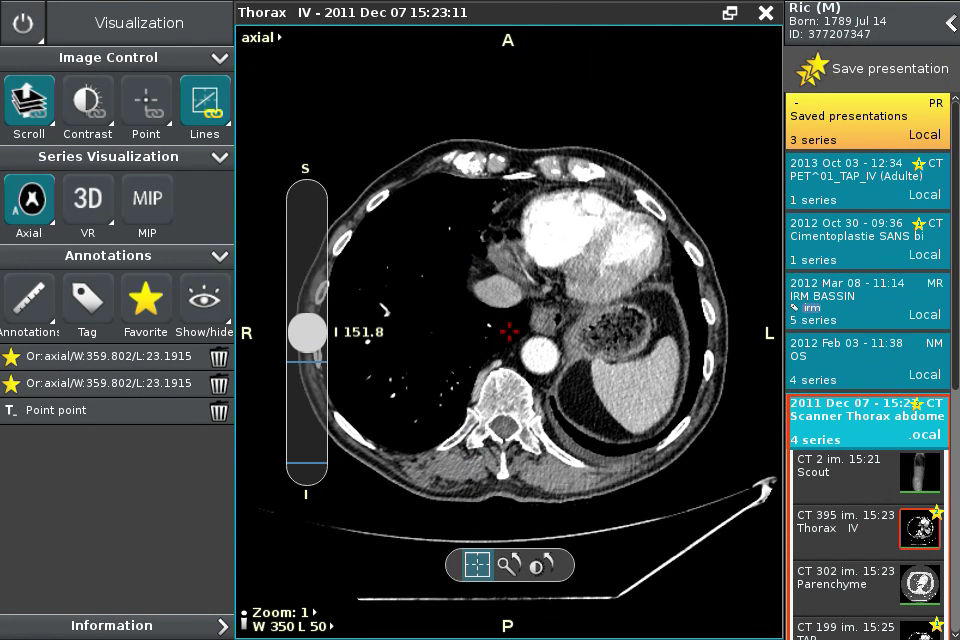

Anywhere Streaming is a DICOM visualization client that connects to Anywhere Server. It provide standard medical image navigation tools surch as : slicing, windowing, MPR, 3D VR, MIP, oblique ...

All standard medical image modalities are supported : MR, RX, CT, PET, NM, MG, US ...

Screenshots